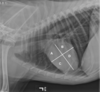

Identify the labeled structures

A = trachea B = carina C = right atrium D = left atrium E = right ventricle F = left ventricle G = caudal vena cava H = aorta I = right crus of the diaphragm J = left crus of the diaphragm